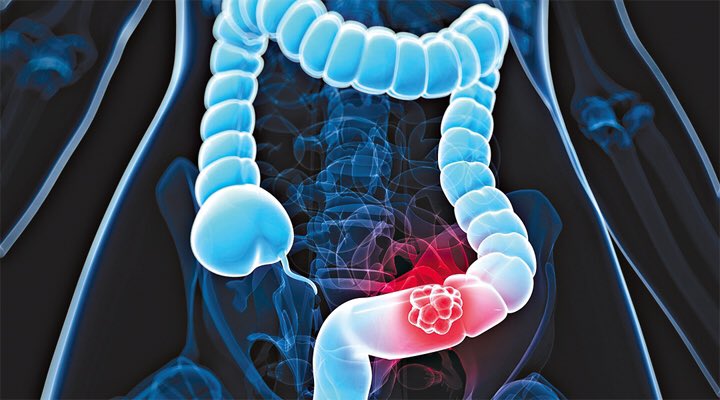

هو مرض مزمن يصيب الأمعاء الغليظة و يسبب تقلصات و انتفاخات في البطن (البطن منتفخ) ، يمكن أن يؤثر على أي شخص في أي عمر ، و تختلف أعراضه بين المصابين بهذا المرض و يُصنف هذا المرض ضمن منطقة الجهاز الهضمي كما هو موضح بالصورة:

المضاعفات التي قد يُسببها هذا المرض :

- بواسير